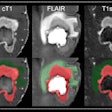

AI can evaluate treatment response for brain tumors